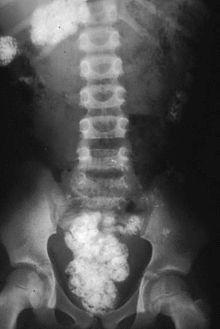

The silica in the soil that has been eaten by a woman shows up as white on this plain X-ray.